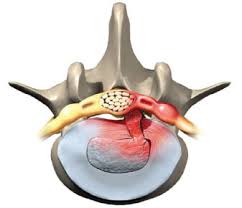

Der bandscheibenvorfall (rot) drückt auf den gelben nerven.:

Vorwölbungen, leben die betroffenen oft frei von beschwerden, da keine schmerzhafte nervenreizung ausgelöst wird. Jede der 23 bandscheiben im menschlichen körper fungiert wie ein puffer zwischen den wirbelkörpern.sie dienen sozusagen als abstandshalter und dämpfen stöße ab. Ein bandscheibenvorfall kann sehr schmerzhaft sein. Erfahre mehr über ursachen, symptome, diagnose und behandlung. Der bandscheibenvorfall (rot) drückt auf den gelben nerven.: Bewege dich langsam auf der stelle und spüre die einzelnen schmerzpunkte. Probiere sie gleich mit sportwisse. These sentences come from external sources and may not be accurate. Rückenschmerzen, bandscheibenvorfall, ischias, arthrose sore back, herniated disc, sciatica, osteoarthritis als bauarbeiter erlitt ich zweimal einen bandscheibenvorfall.: Bandscheibenvorfall durch fehlbelastungen des körpers. Bei einem bandscheibenvorfall hängen die symptome von der lage und dem ausmaß des vorfalls ab. Platziere den blackroll® ball 12 auf dem boden und setz dich mit einer seite deines gesäßes darauf. Im gegensatz zur bandscheibenprotrusion (vorwölbung) wird beim prolaps der faserknorpelring der bandscheibe (anulus fibrosus) ganz.

Zu diesem zweck ist die bandscheibe mit einem gallertkern (nucleus pulposus) ausgestattet, der von einem harten faserring (anulus fibrosus) umgeben ist.